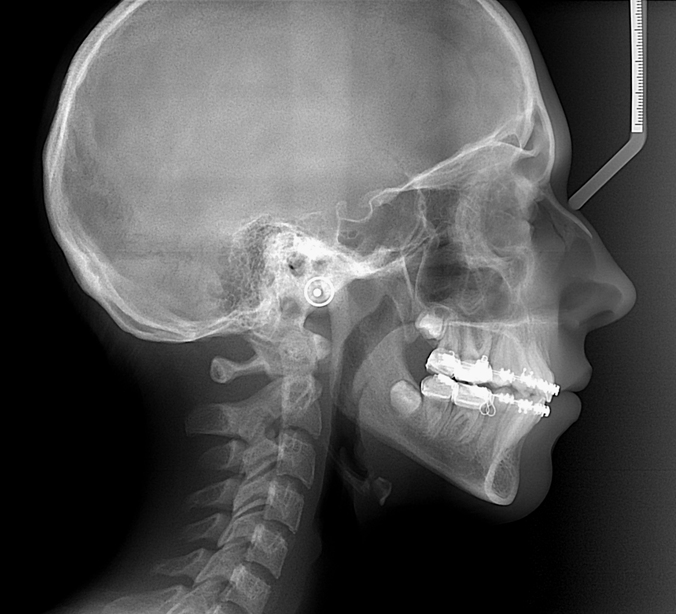

- Pour les téléradiographies, il sera mis dans vos oreilles des embouts métalliques afin que vous soyez parfaitement de profil par rapport à la plaque radiologique et pour vous éviter de bouger. Ces moyens de contention sont totalement indolores. Il vous sera demandé de serrer les dents les plus postérieures et de laisser les lèvres jointes.

TELERADIOGRAPHIES

C’est un examen qui permet de visualiser, en rapport 1/1 (1cm sur le film = 1 cm sur le corps), la tête dans son ensemble en superposant sur un seul film les contours osseux, les dents et les parties molles du visage.

Il est possible de réaliser plusieurs incidences:

a) de profil. C’est l’incidence la plus fréquente.

b) de face,

c) en incidence de Hirtz.

On positionne des embouts métalliques () dans les oreilles afin de nous permettre de vous mettre dans la position souhaitée et de vous aider à la garder et à ne pas bouger.

Cet examen est fait le plus souvent chez l’enfant dans les bilans d’orthodontie.

Il peut être fait également chez l’adulte dans la même indication.

Bilan préchirurgical pour rétrognatisme. La mandibule est en situation trop postérieure par rapport au maxillaire supérieur.